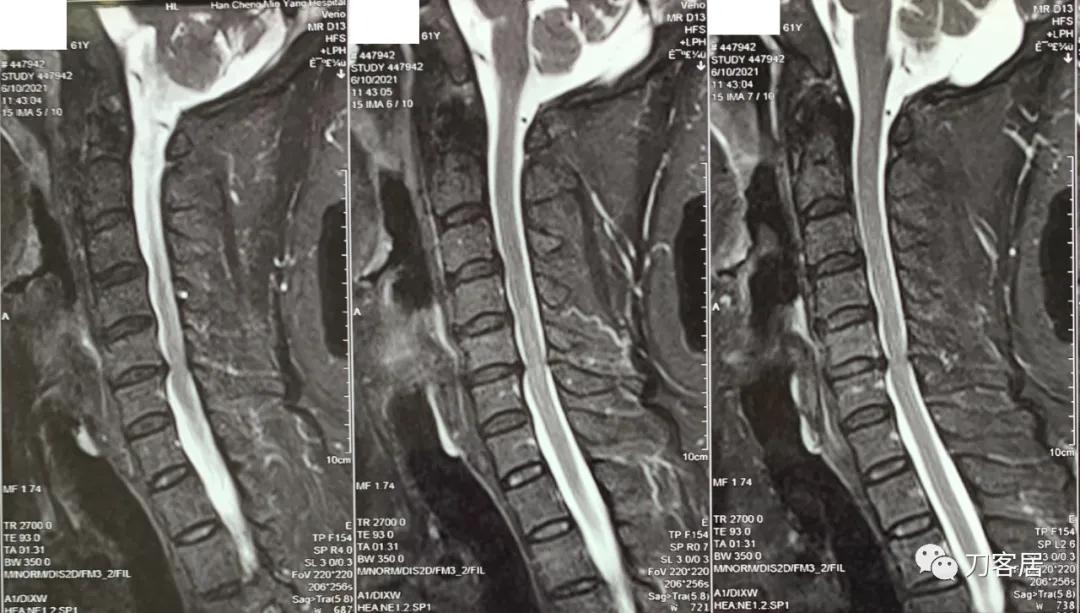

自带颈椎MRI显示颈5-6椎间盘突出,黄韧带肥厚,椎管狭窄,脊髓受压较重,但目前症状较轻,无明确神经损伤表现,暂不考虑手术。

诊断:颈椎间盘突出,黄韧带肥厚,椎管狭窄。

图1. 20210610韩城医院颈椎MRI矢状面T2相1,提示颈5-6椎间盘突出,黄韧带肥厚,颈5-6椎管狭窄。

图2. 20210610韩城医院颈椎MRI矢状面T2相2,提示颈5-6椎间盘突出,黄韧带肥厚,颈5-6椎管狭窄。